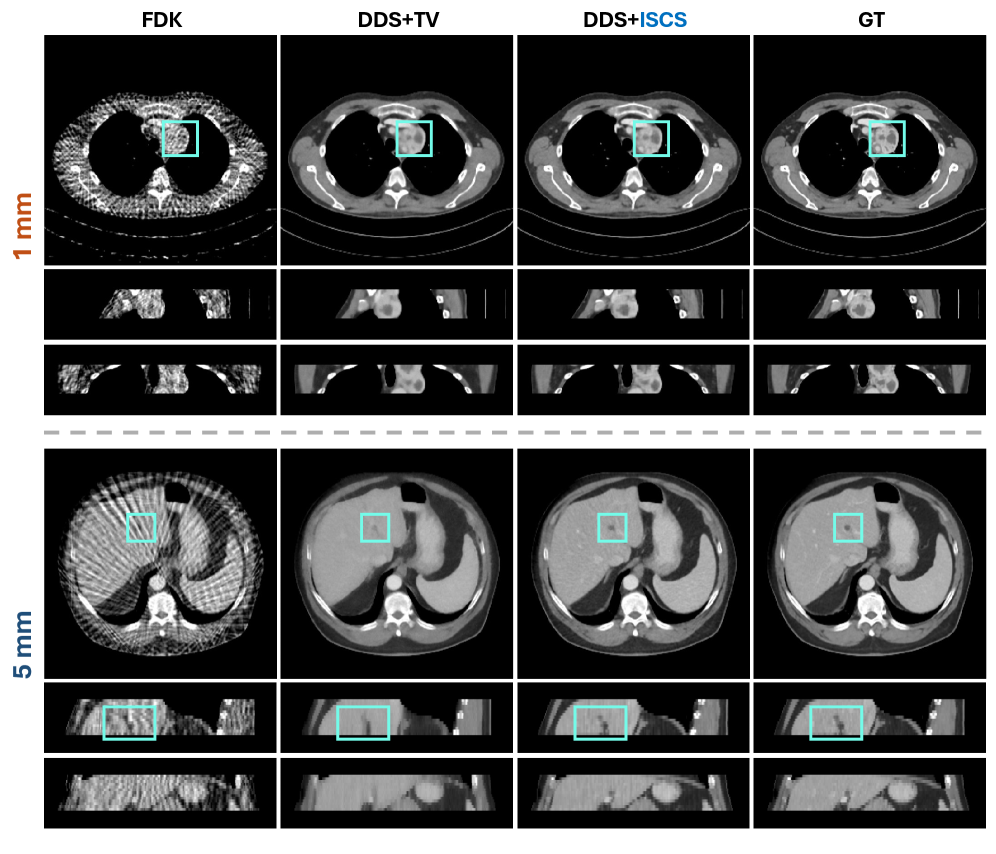

Validation on DeepLesion Dataset. We empirically validated this hypothesis using the DeepLesion dataset. We selected two representative subjects: Case A (1mm slice with a large lesion) and Case B (5mm slice with a small lesion). The visual results in Fig. 6 indicate:

• Case A (Large Lesion, 1 mm): ISCS successfully reconstructed the sharp boundaries and internal texture of the large tumor, demonstrating that Slerp interpolation in noise space does not blur structural transitions.

• Case B (Small Lesion, 5 mm): We observed that TV regularization, in its effort to enforce inter-slice intensity consistency, nearly obliterated the small tumor. In contrast, ISCS preserved the small lesion with high fidelity, yielding a result closest to the GT.

These results confirm that ISCS is robust in pathological scenarios, avoiding the detail destruction common in strong explicit smoothness regularizers.

Refer to caption

Figure 6: Qualitative comparison of compared methods for SVCT of 30 views. Two representative subjects with slice thicknesses of 1 mm (top) and 5 mm (bottom) are shown. Cyan boxes mark the lesion regions. The display window is [-175, 275] HU.